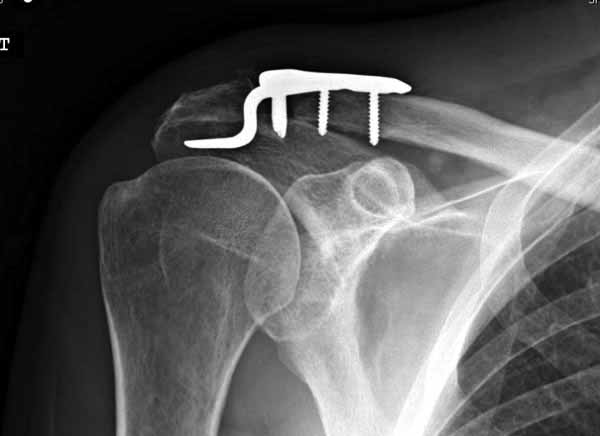

foto 3

3.JPG

14KB (15209 bytes)

Замечание понял, спасибо и нормальные рентгенограммы, молодец!

Вопрос "ключичной пластины с крючком при акромиальных переломах" я буквально понял, что ведется разговор насчет перелома акромиального отростка, т.е. самого акромиона. И поэтому ссылка на Acumed, они делают пластину для акромиона!

Во вторых, это хорошо что нашли длинную пластину, я об этом писал "пластина короткая, не покрывает медиальный диафизарный фрагмент ключицы", и у нас не получилось, пластина не выдержала...

А вообще можно было показать рентген и задать прямой вопрос, что разговор ведется насчет косых переломов акромиального конца ключицы. Не точный вопрос, "угадайка" - привел к заблуждению.